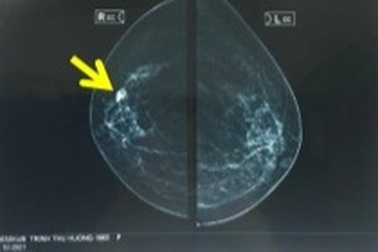

Nhiều trường hợp phát hiện ung thư vú khi tình cờ đi khám sàng lọc miễn phíNgười phụ nữ 58 tuổi ở Hà Nội không có dấu hiệu gì của ung thư vú, nhưng được con đăng kí khám miễn, khi đến viện khám, bác sĩ phát hiện khối u vú phải kích thước 1,5cm.